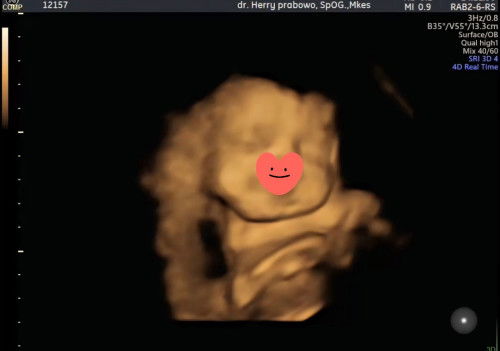

4 d bun cumn klok di rs tmpt aku usg aku biasanya bayar untuk usg 3d tpi nnti pas di ruangan dokternya kasih tunjuk muka si adek pakek gmbar 4d dan itu bolh di foto sama kita tergantung dokternya juga dan juga yg di cetak hasil ush 3d

di pojokan ada itu bu yg tulisan warna ungu, angka dan huruf

3D, klo video 4D

4 dimensi bun